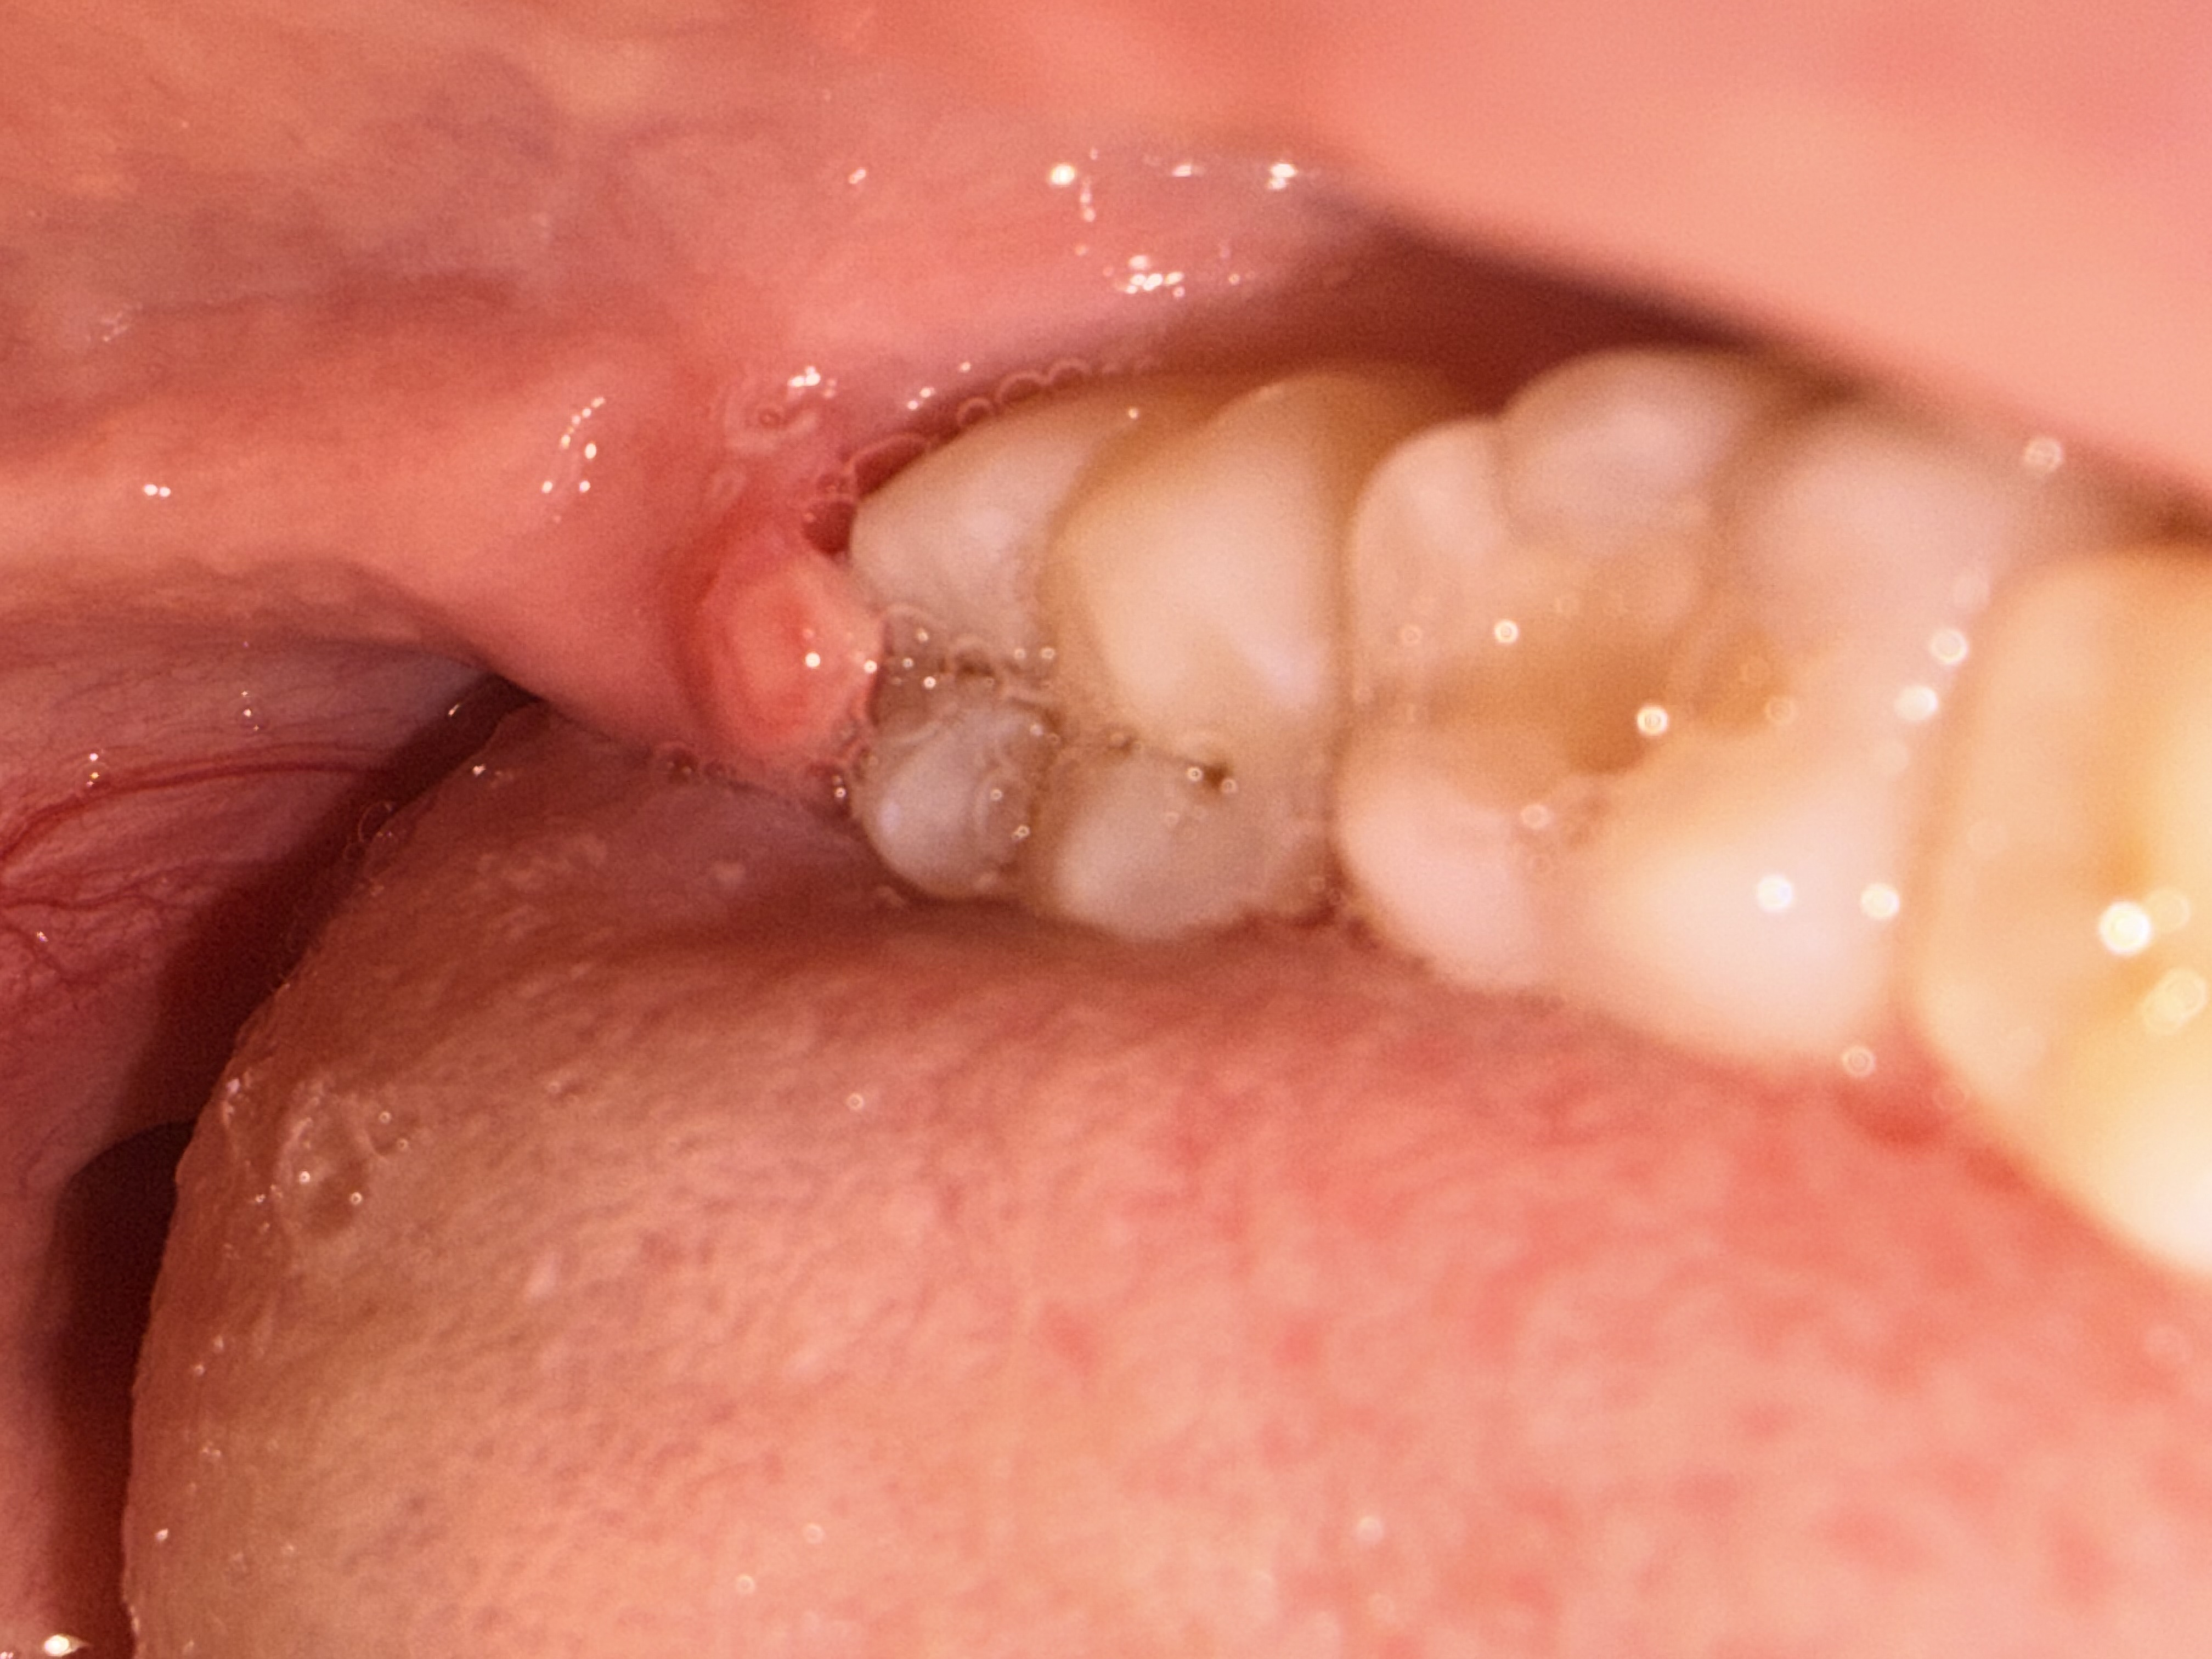

Het tandvlees bij mijn verstandskies komt los en begint steeds te ontsteken. Ik moet volgende maand mijn verstandskiezen laten en trekken en dan moet het verholpen zijn zegt mijn tandarts. Normaal word het flapje rood en opgezwollen en na 3 a 4 dagen is het weer hersteld als ik perio aid gebruik. Nu heb ik er al een week last van en begint het flapje er ook raar uit te zien. Nu zit er iets wits omheen en gister was het knalrood. Ik weet niet zo goed wat ik ermee aan moet, het doet namelijk ook best veel pijn. Mijn eigen tandarts is op vakantie en de vervangende zit helemaal vol, vandaar dat ik de vraag hier maar stel. (De foto’s staan als het goed is met de eerste maandag tot vandaag de laatste foto)